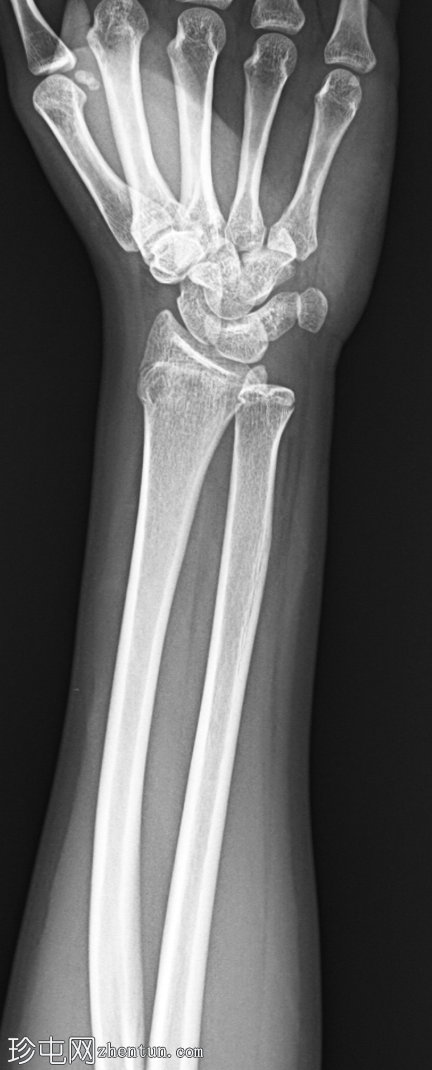

侧位片

左腕正位X线片显示桡骨远端干骺端背外侧皮质轻微弯曲,无皮质破裂或移位。无明显成角畸形或尺骨骨折。关节间隙和腕骨排列正常。

最终诊断:桡骨远端干骺端轻微嵌插(弯曲型)骨折。